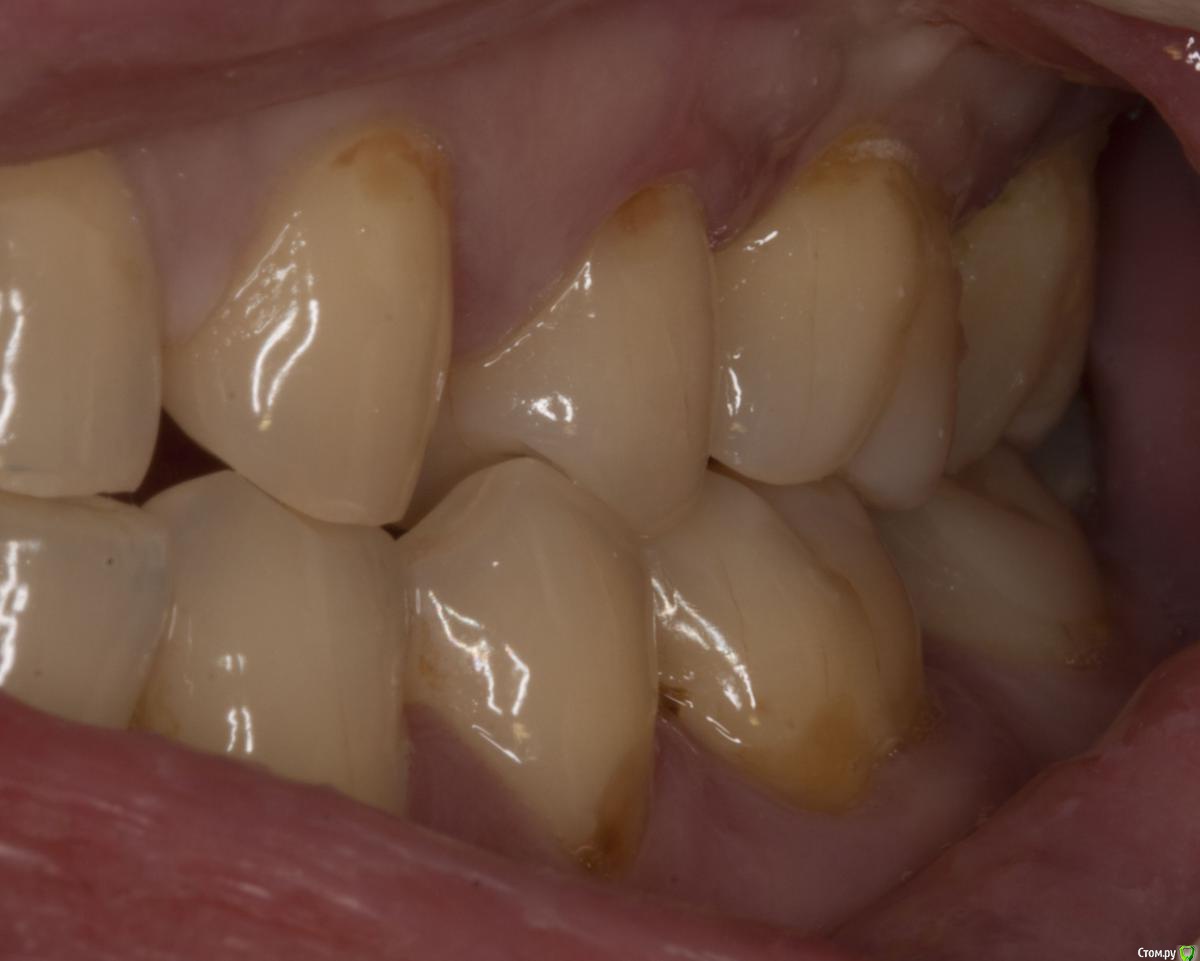

M@estro Опубликовано 29 июля, 2015 Поделиться Опубликовано 29 июля, 2015 (изменено) Травматический узел. Изменено 29 июля, 2015 пользователем M@estro 10 Ссылка на комментарий

M@estro Опубликовано 3 августа, 2015 Поделиться Опубликовано 3 августа, 2015 но у вашем случае у антагониста пломба, а у паца тс нет пломбы на антагонисте. или там другая причина супраоклюзии? Я специально сделал серию фото, чтобы виден был перегруз 2.6 при левой латеротрузии. Ссылка на комментарий

M@estro Опубликовано 30 июля, 2015 Поделиться Опубликовано 30 июля, 2015 Паш, расскажи подробнее пожалуйста Пришла пациентка на прием, болит зуп. Сделали снимок , карман локально до 1 см глубиной. Подвижность 3 степени, обострение. Зуб целый. Ну челюстью подвигала - оппа! - вот и привет. Причем призналась. что сресяк у нее месяца 4 -5 усилился, вот и окончательно не выдержал. Вторая была девушка - тоже 2.6 зуб, но я не фотал её. Ситуация похожая, я тоже зуб вынул просто. Там вообще был целый моляр, ни дырочки в нем, ни пломбы. Год лечили от гайморита антибиотиками её лоры, потому как " все зубы интактные" . В поликлише в смотровом проглядели её этот зуб. Я удалил - через две недели пришла на приём с благодарностью - разложило нос ) Видел недавно её - гайморита нет и следа. Ссылка на комментарий

bogdan_r Опубликовано 30 июля, 2015 Поделиться Опубликовано 30 июля, 2015 но у вашем случае у антагониста пломба, а у паца тс нет пломбы на антагонисте. или там другая причина супраоклюзии? Ссылка на комментарий